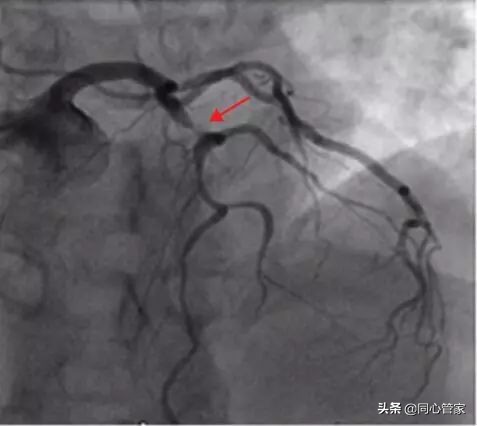

冠脉造影一直被人们称作冠心病诊断的“金标准”,尤其是有心血管疾病、做过支架的患者对造影检查再熟悉不过了。但是今天小编为大家介绍的这种检查,仅需3秒钟就能将血管中的结构、斑块性质、血栓“看”的比造影还清楚——它就是“OCT(中文名称:光学相干断层扫描)”。

如果,将我们的血管比喻成“隧道”,里面坑坑洼洼,有的地方是宽敞的双车道,有的地方窄的只能侧身通过,还有的地方有塌方风险,但具体情况不清楚。这时候我们使用“冠脉造影术”检查时可以将整个“隧道”里面的宽敞、狭窄路段探查清楚;但是“具体狭窄”的位置以及危险程度却还不明确。这时就是“OCT(中文名称:光学相干断层扫描)”大显身手的时候了,它就像眼睛一样带我们了解血管里的情况。

冠脉造影:在平时,冠脉造影是诊断冠心病最常用有效的方法,但它只是一个二维平面图像存在一定的局限性,没法让我们了解血管里面发生的情况。